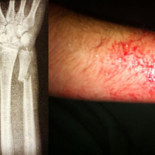

1175

meneos

4123

clics

Menor con un brazo roto por un golpe de porra de los antidisturbios [CAT]

mnm

|

etiquetas

:

policía

,

mossos

violencia

14n

agresión

54 comentarios